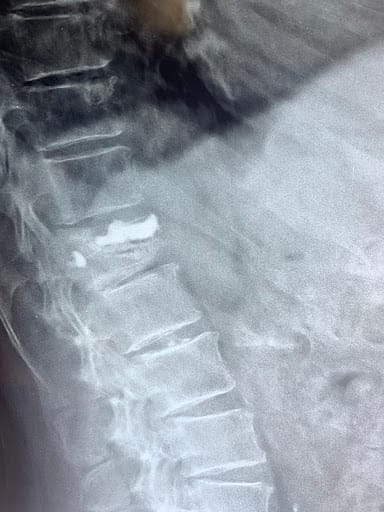

These are relatively common fractures in elderly individuals as the spine is one of the first bones to lose bone density and the mechanics of the spine is such that the lack of bone strength can often result in spine fractures even with little to no injuries to the spine. Hence, even the simplest of manoeuvres to a weak spine such as bending forward to pick up weight (without an actual history of falls or trauma to the body) can leave the spine most vulnerable to osteoporotic stress fractures. Similarly, in the case of falls/ injuries, the loading weight on the spine in addition to the force of injury that the individual's spine is susceptible to can result in compression fractures.

Non-operative management for simple wedge compression fractures which have retained significant height even after the compression and do not pose a threat to the spinal cord or risk of progressive spinal deformity.

In case of stable spine fractures which pose no threat to the spinal cord but cause severe prolonged pain of the back, an alternative minimally invasive option of treatment involves a day care procedure known as Vertebroplasty or kyphoplasty under local Anaesthesia.